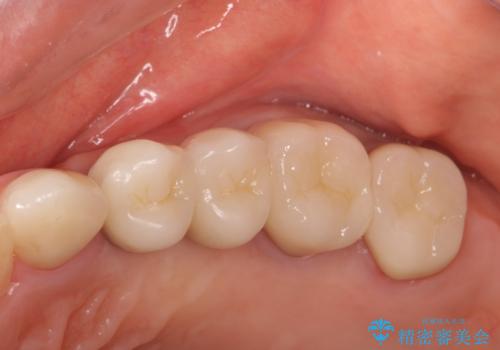

銀歯を外してのインプラント・セラミック治療

ただ銀歯を外してセラミックにするだけではなく、長期的な観点に立ち長持ちするような環境を整備できるよう心がけ歯科治療をおこなっております。

- 123.2万円(インプラント×2・チタンカスタムアバットメント×2・ジルコニアクラウン×4・仮歯×4)費用は治療当時の料金となります